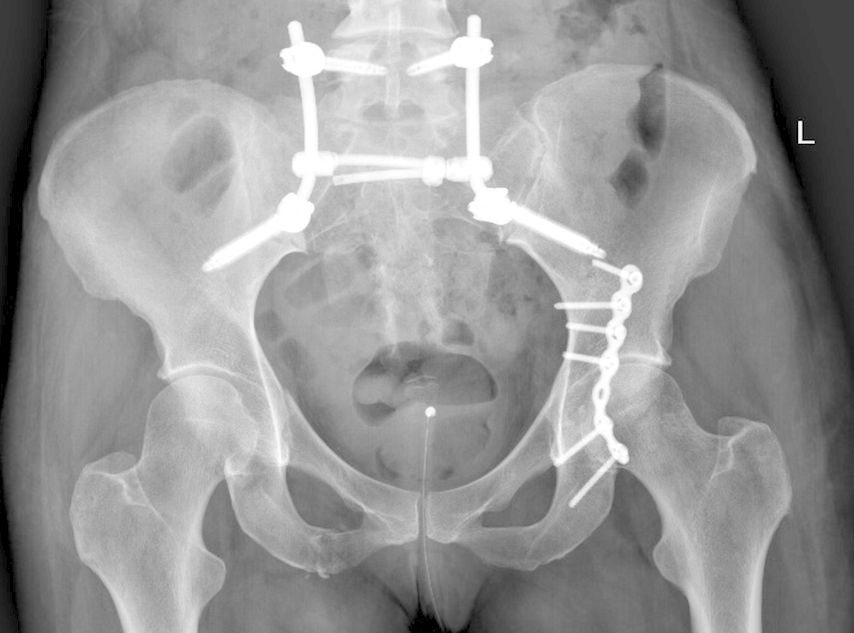

Abb. 1: Beckenübersicht einer 48-jährigen Patientin mit lumbopelviner Stabilisierung und Acetabulumplattenosteosynthese nach Sturz aus großer Höhe mit lumbopelviner Dissoziation und mehrfragmentärer transforamineller Frakturkomponente, oberer und unterer Schambeinastfraktur rechts und Acetabulumfraktur links